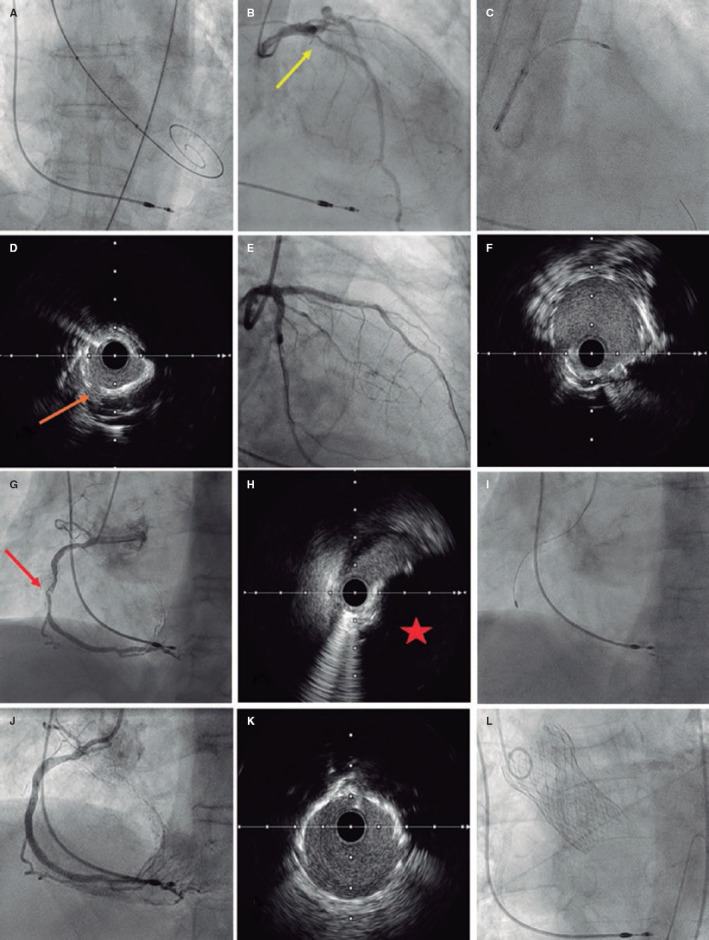

Abstract Image